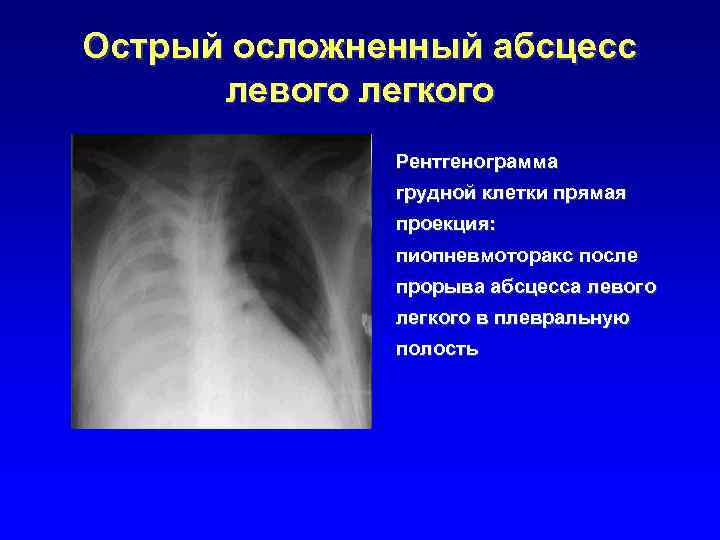

Острый осложненный абсцесс левого легкого Рентгенограмма грудной клетки прямая проекция: пиопневмоторакс после прорыва абсцесса левого легкого в плевральную полость